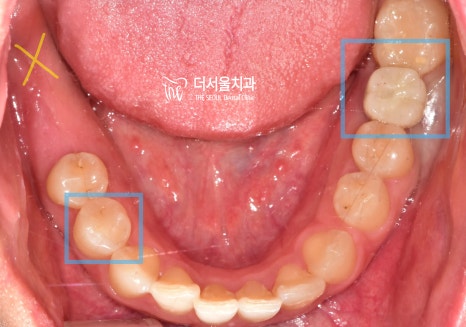

초진 사진을 보면

상실된 치아는 물론이며

잔존 치근, 충치

여러 문제들이 얽히고설켜있었습니다.